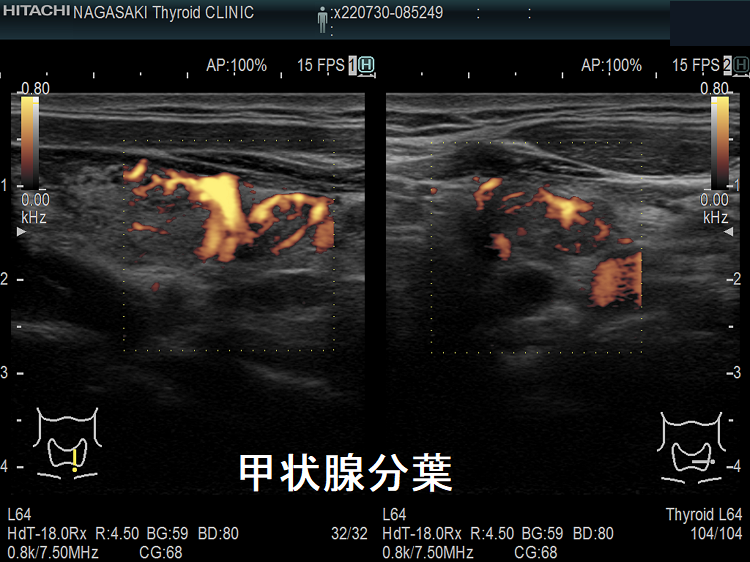

頚部異所性甲状腺でなく甲状腺分葉

頚部異所性甲状腺のように見えても、微妙に甲状腺本体と連続していて甲状腺分葉の場合があります。

甲状腺分葉 超音波(エコー)画像

甲状腺分葉 超音波(エコー)画像 ドプラーモード